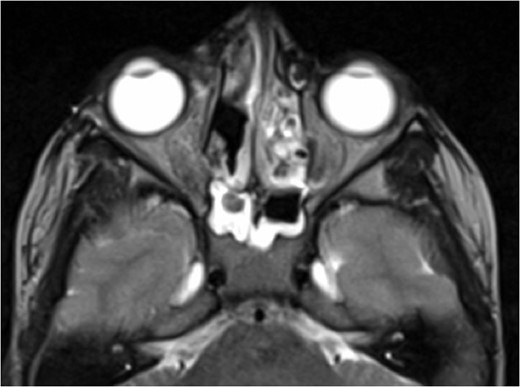

Axial T2 weighted sequence demonstrating the presence of multiple fluid filled levels (short white arrow) within the expansile lesion and smaller cyst present within the larger cyst (long white arrow).

Axial T1 post-contrast sequence with fat suppression demonstrating peripheral enhancement (white arrows) but no internal or solid enhancing components to suggest that this is a secondary ABC.

At this point the MRI was reviewed and the possibility of an ABC was raised. This was due to the presence of fluid–fluid levels, cyst within a cyst appearance and lack of restricted diffusion within the sinonasal contents and material drained at the time of the first endoscopic procedure. He was discharged home on oral co-amoxiclav, and topical betamethasone nose drops.